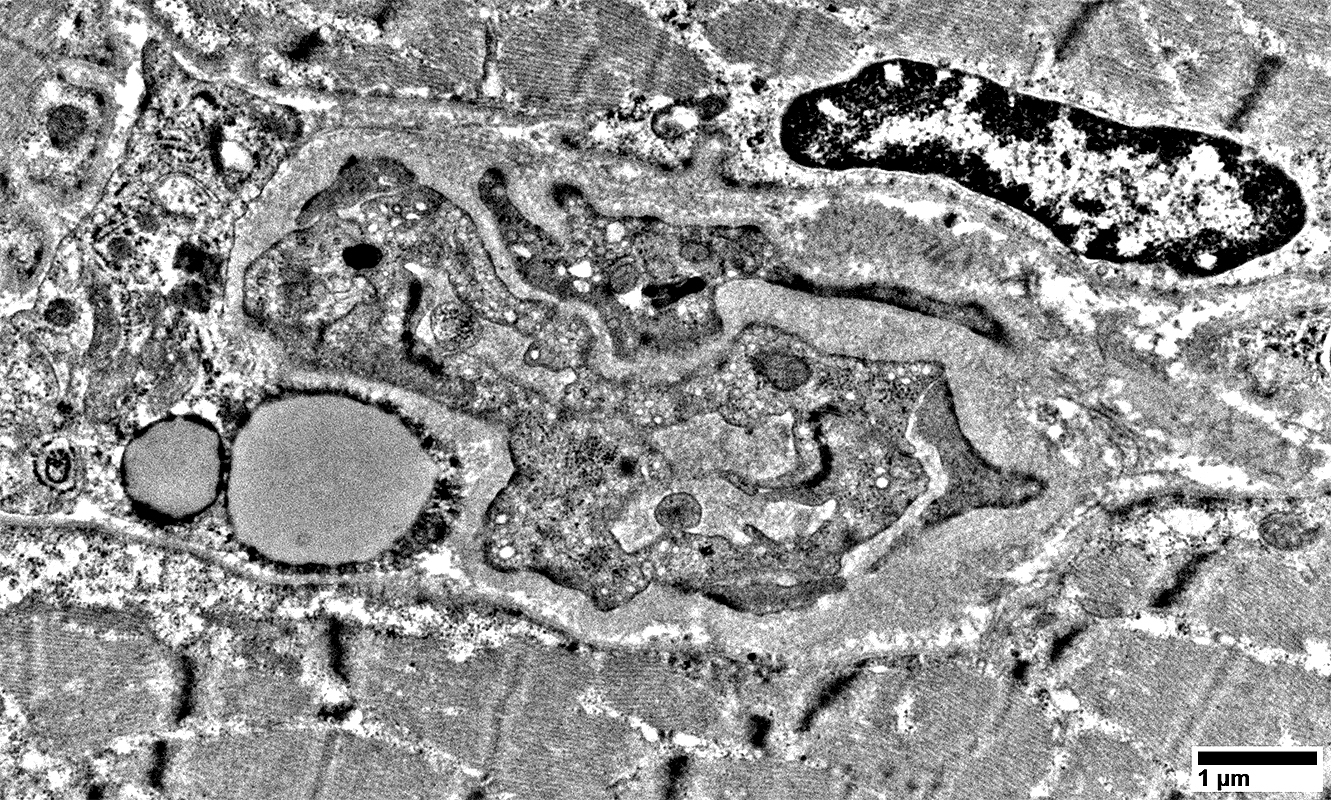

MELAS: Mitochondrial Ultrastructure

From: R Schmidt

Pericytes   Mitochondrial proliferation & enlargement (Black arrows)

Endothelial cells   Multiple small vacuoles (White arrows)

Large cells near vessels with

Mitochondrial proliferation & enlargement

Lipid droplets

Mitochondrial proliferation between sarcomeres

Mitochondrial proliferation & enlargement: Beneath muscle fiber surface